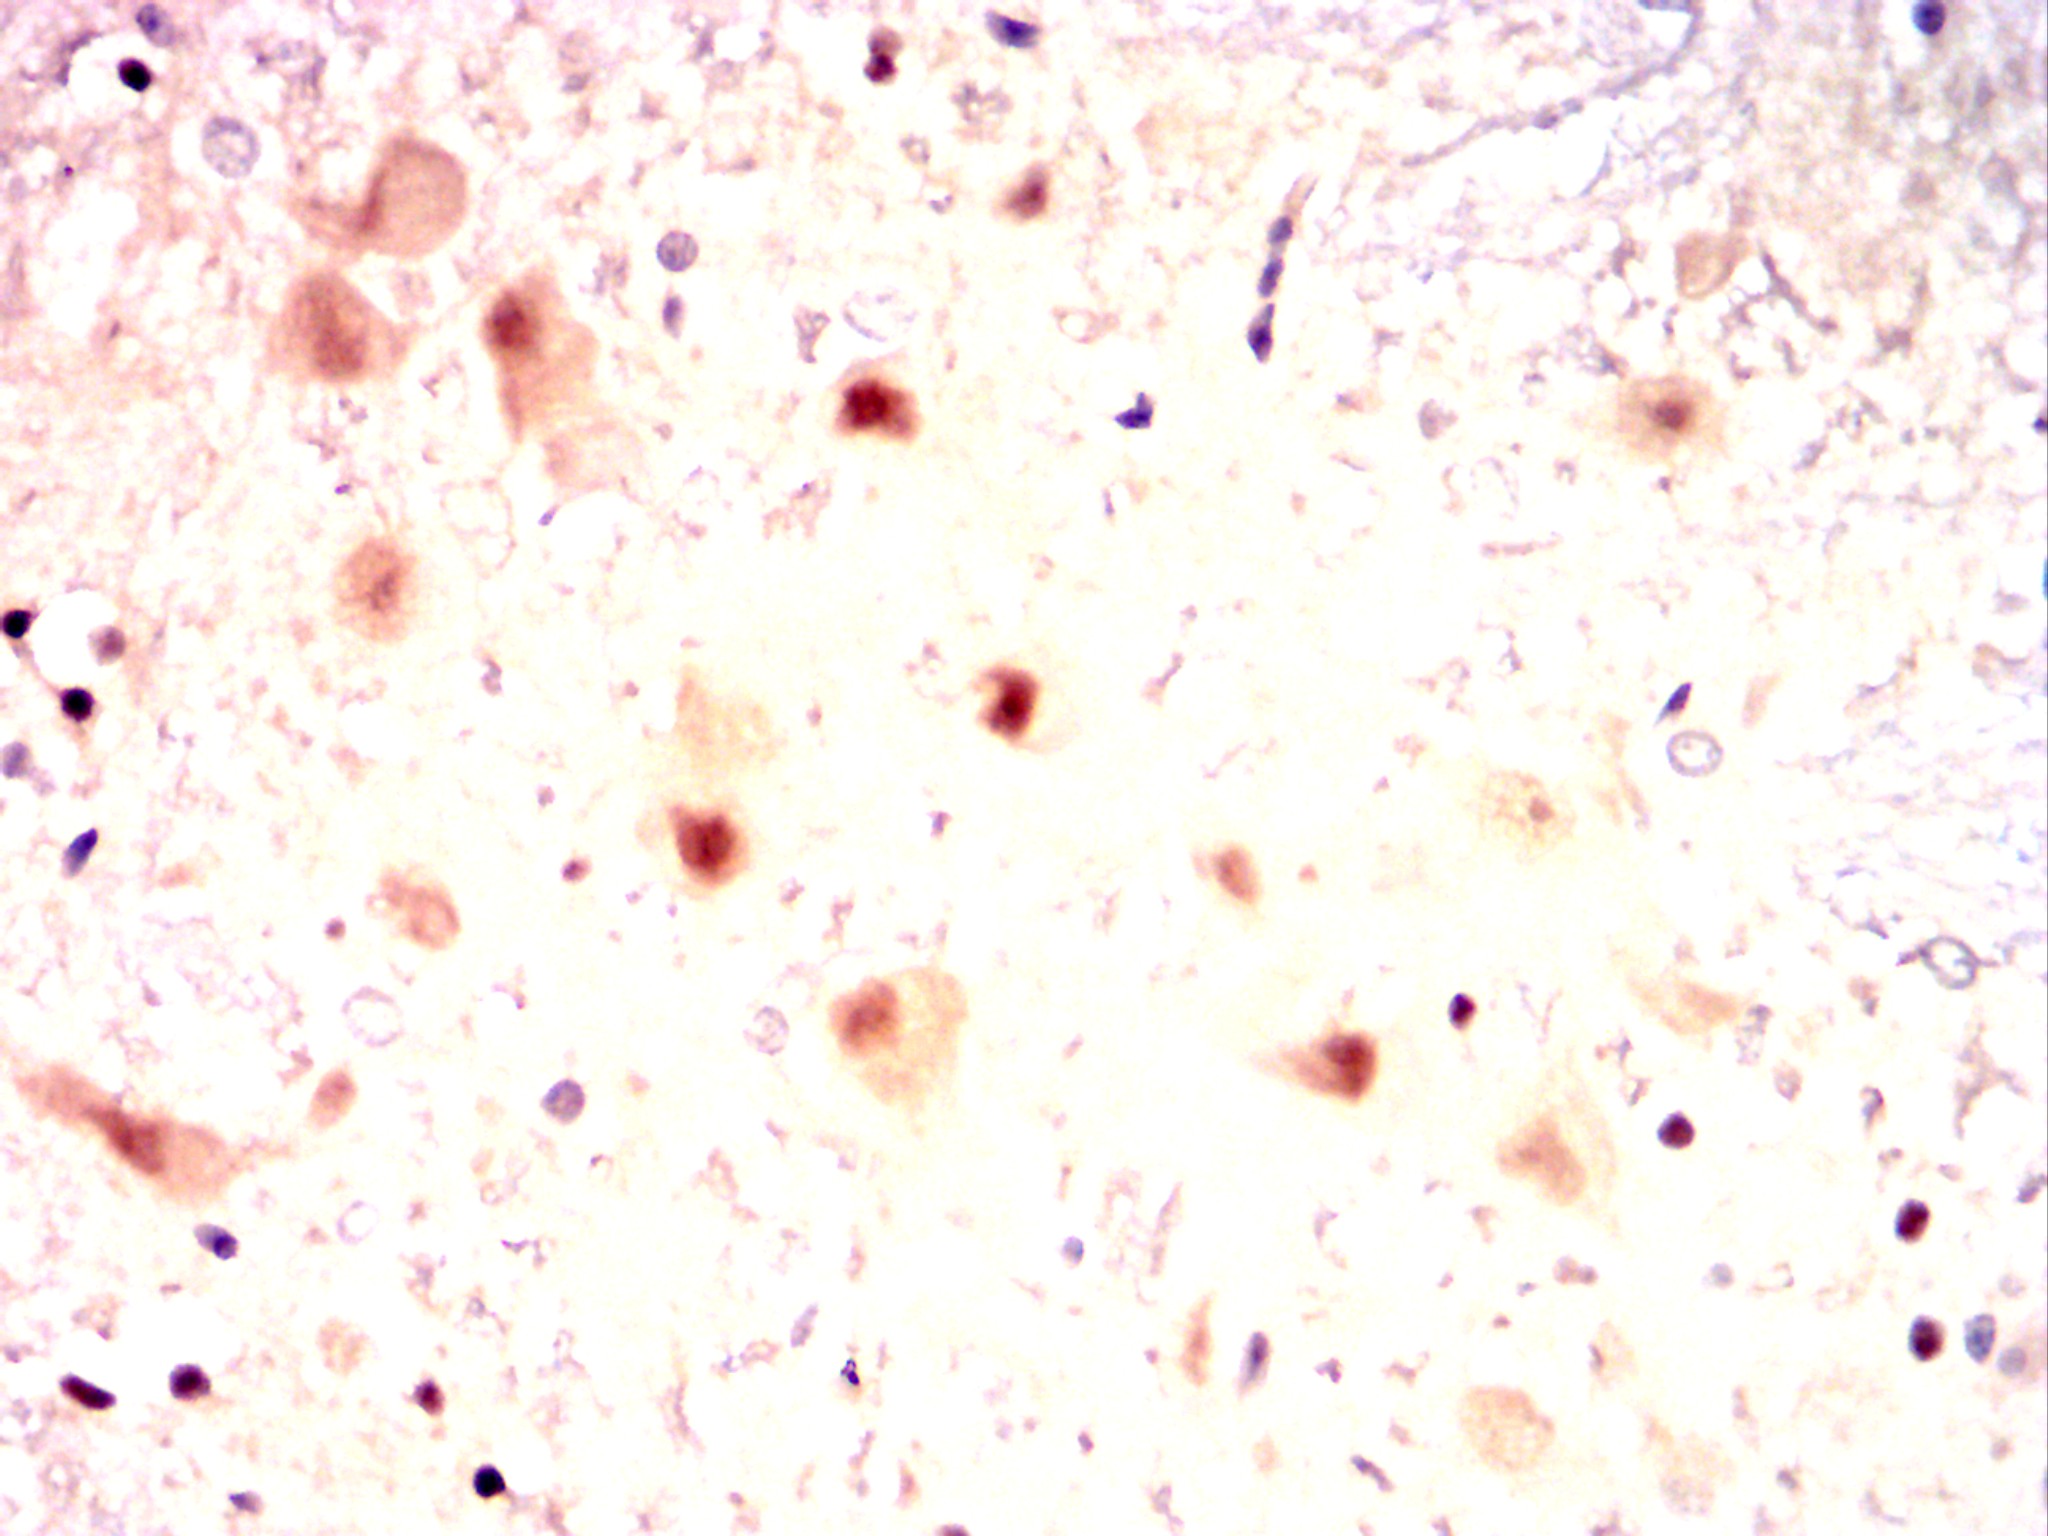

IHC 1/100 - 1/500 Human,Mouse,Rat,Rabbit

Antibodies against CSNK2A2 are widely used to study its expression, localization, and activity in physiological and pathological conditions. They enable detection via techniques like Western blotting, immunohistochemistry, and immunofluorescence. Research highlights CK2's involvement in cancer, where its overexpression is linked to tumor progression and therapy resistance, making CSNK2A2 a potential therapeutic target. Additionally, CSNK2A2-specific antibodies help explore CK2's role in neurodegenerative diseases, viral infections, and developmental processes. Validation of these antibodies is critical to ensure specificity, given the structural similarity between α and α' subunits. Overall, CSNK2A2 antibodies serve as essential tools for dissecting CK2 biology and its implications in disease mechanisms.